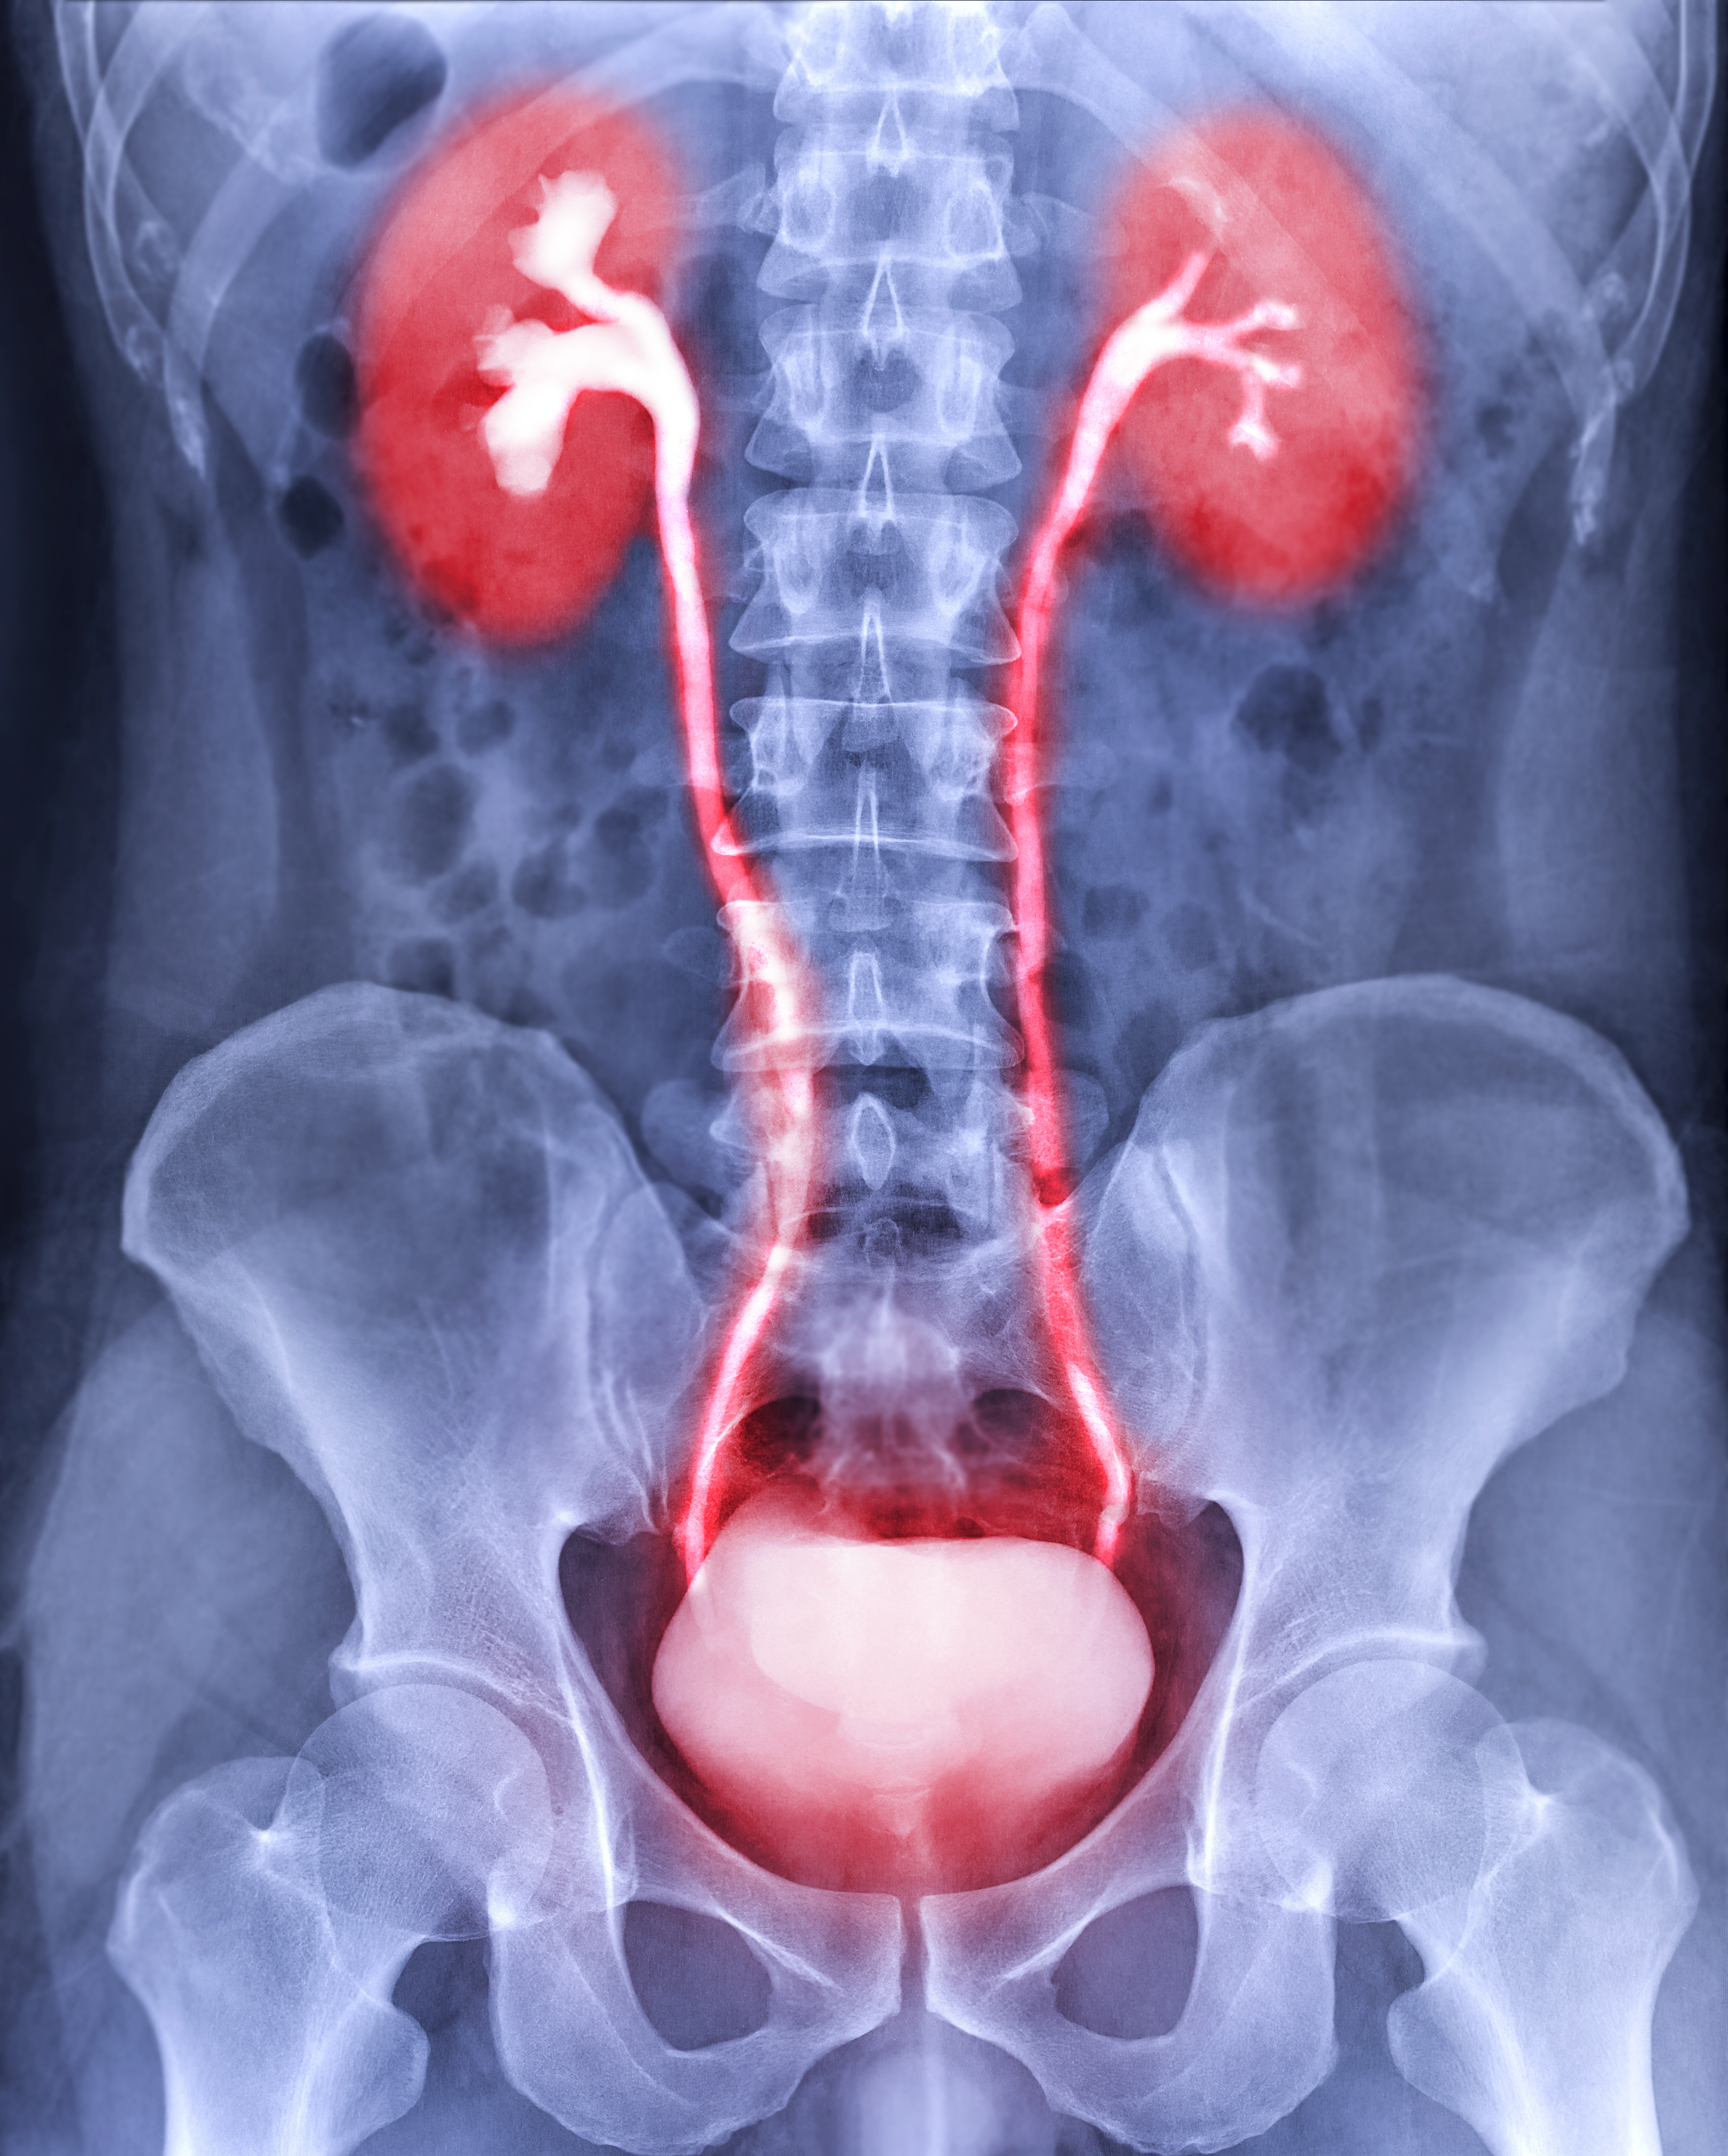

The selection of a contrast agent should reflect the diagnostic purpose, patient condition, and delivery route. Routine CT examinations of the chest, abdomen, or pelvis typically employ low-osmolar nonionic agents in the 300–350 mg I/mL range, injected at 3–4 mL/s. CTA protocols often favor 350 mg I/mL at 4–5 mL/s to achieve rapid vascular enhancement. Intrathecal procedures require low-concentration nonionic agents (180–240 mg I/mL) with minimal osmolality to prevent neurotoxicity. For patients with elevated renal risk or hemodynamic instability, iso-osmolar iodixanol is often chosen despite its higher viscosity because of its superior renal and cardiovascular tolerability.

Contrast-induced nephropathy remains an important concern in radiology practice. The likelihood of renal injury correlates with total iodine dose, osmolality, and individual patient factors such as dehydration, diabetes, and baseline kidney disease. Mitigation strategies include using the lowest effective iodine dose, ensuring adequate hydration before and after the procedure, avoiding multiple contrast exposures within 24–48 hours, and substituting alternative imaging modalities (ultrasound or MRI) when feasible.